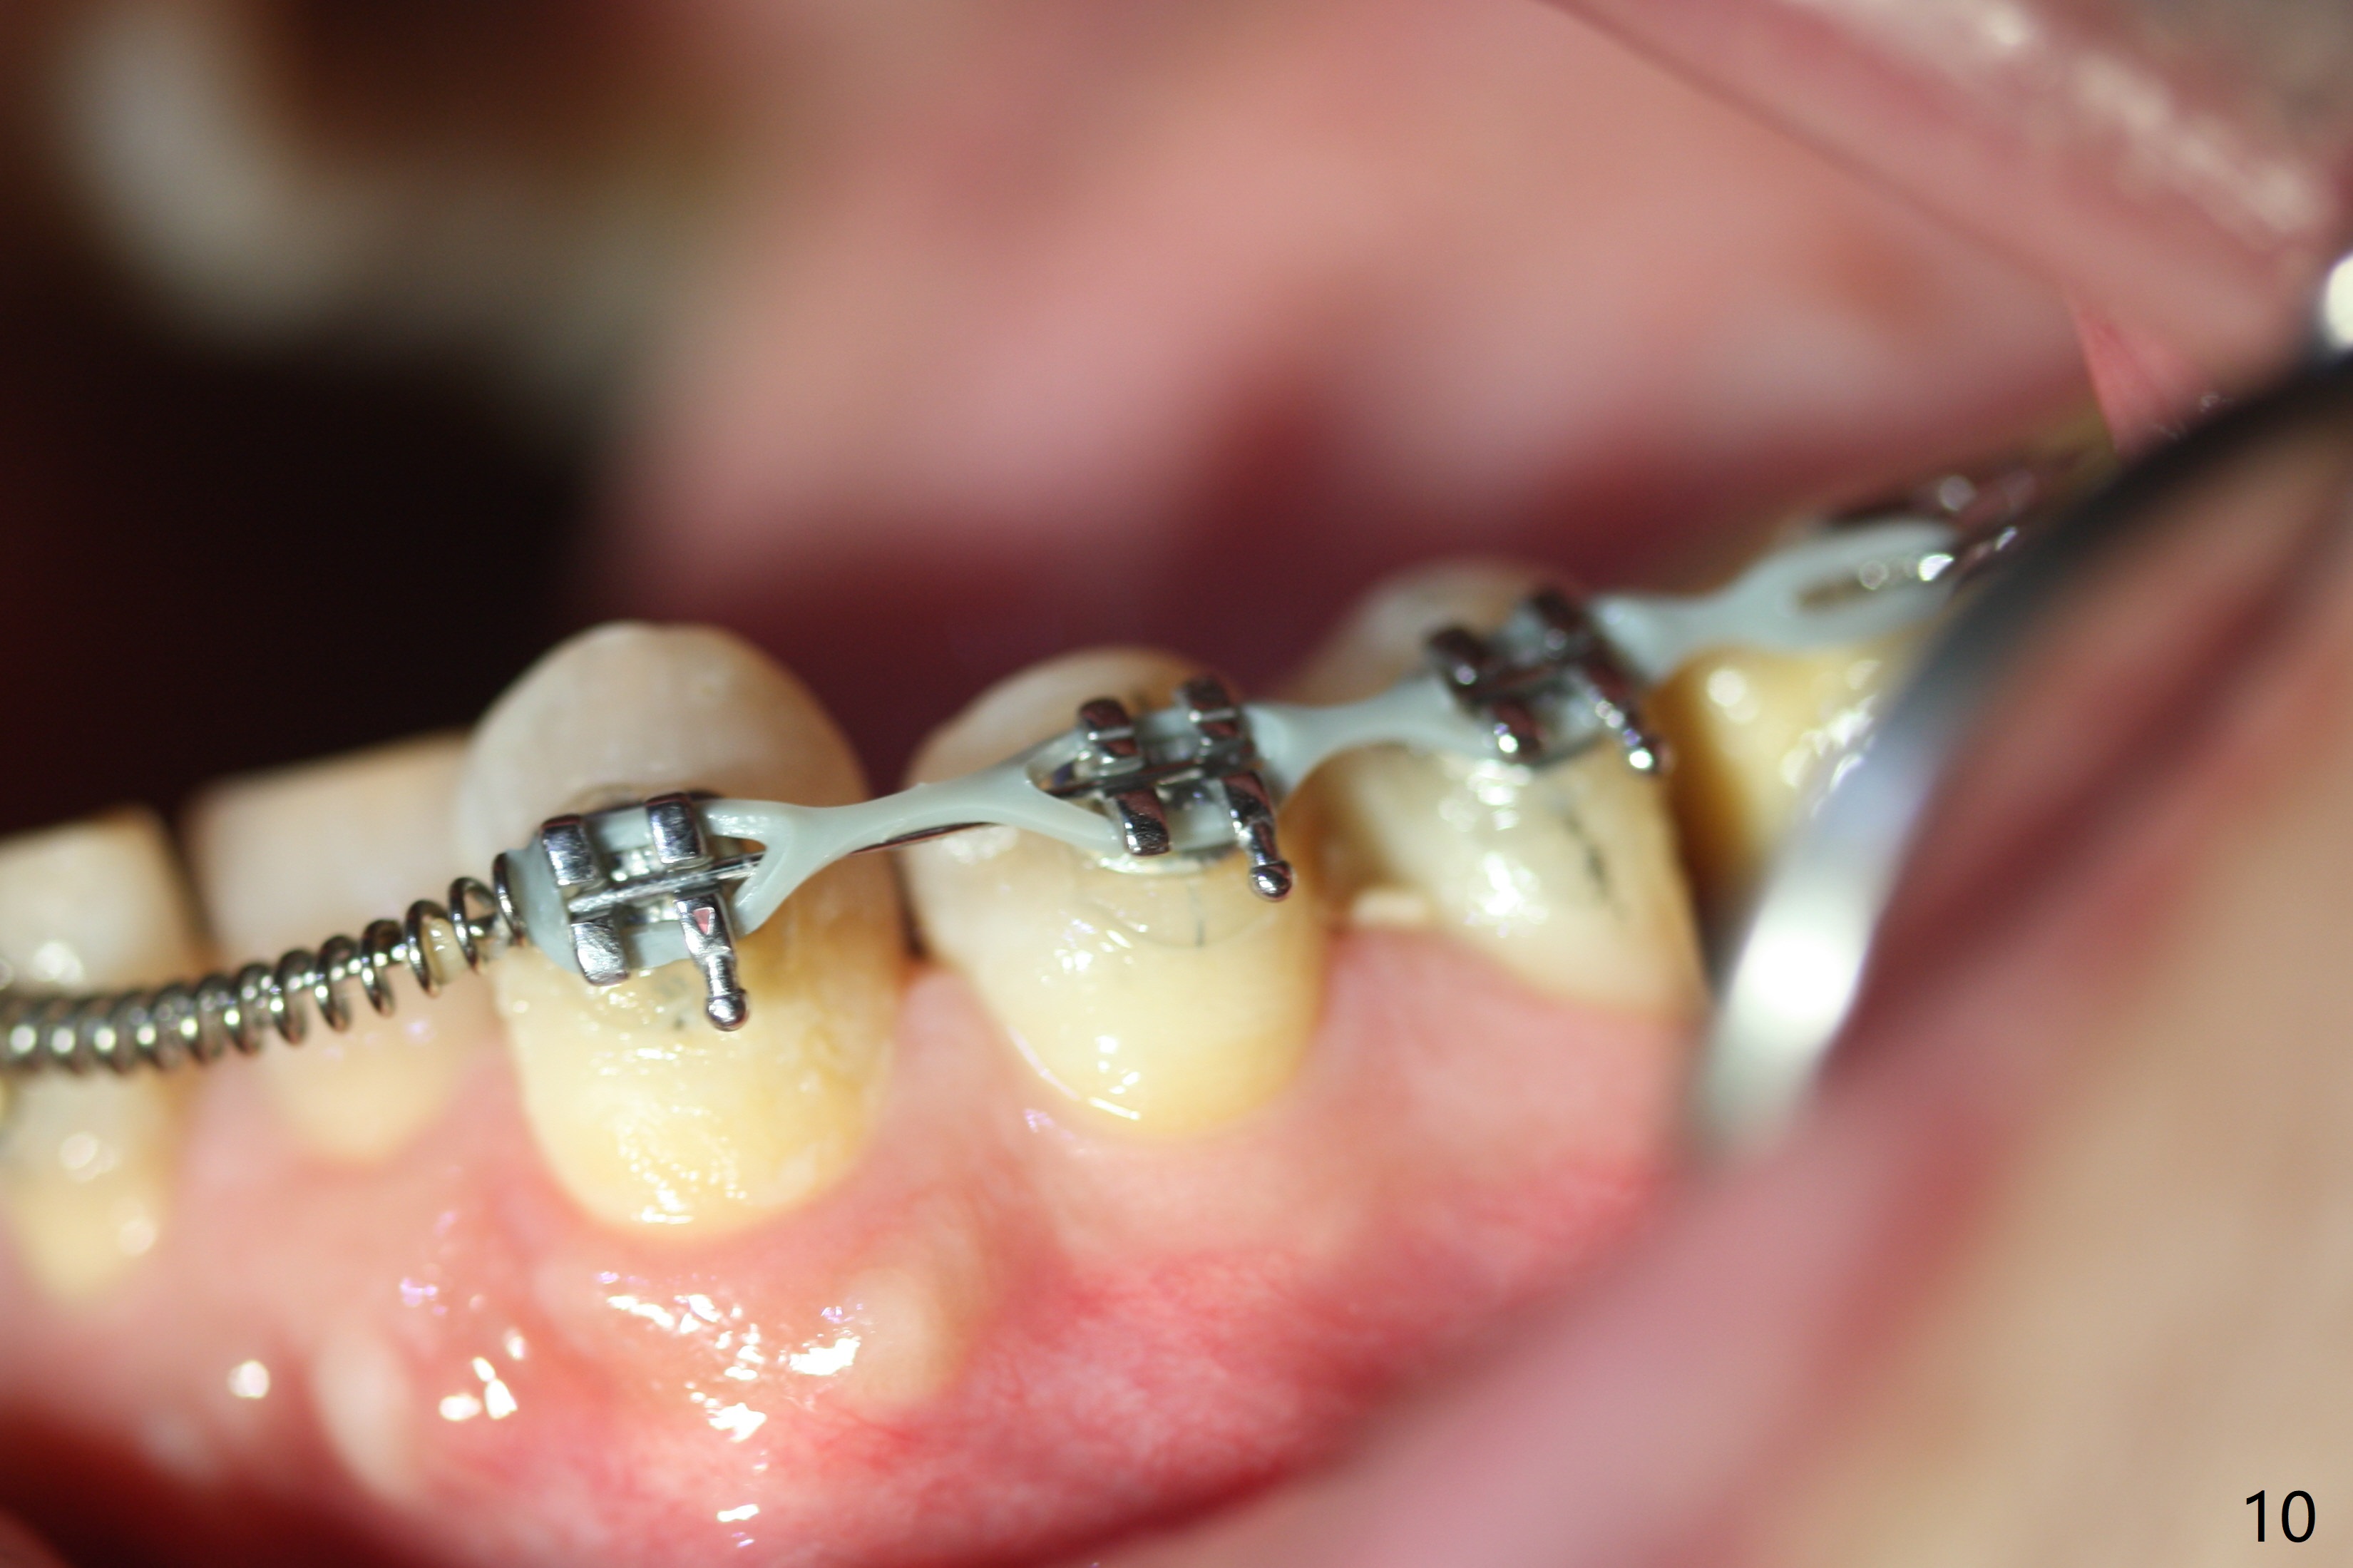

Two weeks post provisionalization over implants at #18 and 19 (4.5 months postop), acrylic is added to the provisional (Fig.1 *) and composite is placed on the other side (Fig.2 *) for clearance (Fig.3). Six days post bracketing, the diastema between LL5 and 6 decreases (Fig.4 between arrows, as compared to Fig.3), suggesting uprighting and distalization of the affected tooth. The diastema increases by trimming the mesial surface of LL6 provisional (Fig.5 *) prior to power chain placement. More acrylic is added to the occlusal surface of LL 6 and 7; more composite to that of UR3 (as compared to Fig.2) for clearance. Power chains change every week. LL5 is uprighted and distalized 1.5 months post banding (Fig.6,7 (14 niti)). Anterior brackets will be placed to correct LL2 cross bite next visit. Three weeks post open coil spring (5 months post initial banding), there is a space between LL2 and 3 (Fig.8) and between LL3/4 (Fig.9). The latter reduces instantly post power chain between LL3 and 6 (Fig.10). There is enough space for LL2 and sling shot is used to correct the cross bite 6.5 months post initial banding (Fig.11). The cross bite is corrected in 1.5 months after occlusal clearance is established (Fig.12). The lower left alignment is within normal limit, although in cross bite with the opposing dentition, immediate post molar crown cementation (Fig.13).